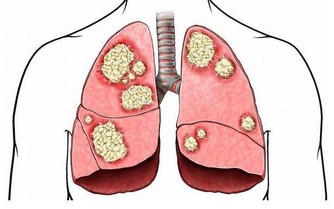

如果是在6個小時以上,死亡風險會比久坐小於6個小時的人要大。超過10個小時,會增加心血管疾病的發生危險。